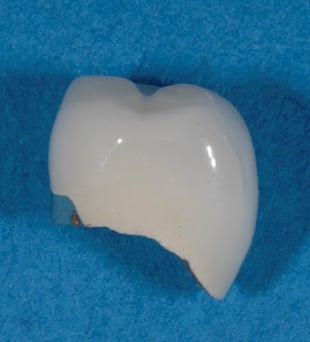

ジルコニア・オールセラミックス・ラミネート・ベニア